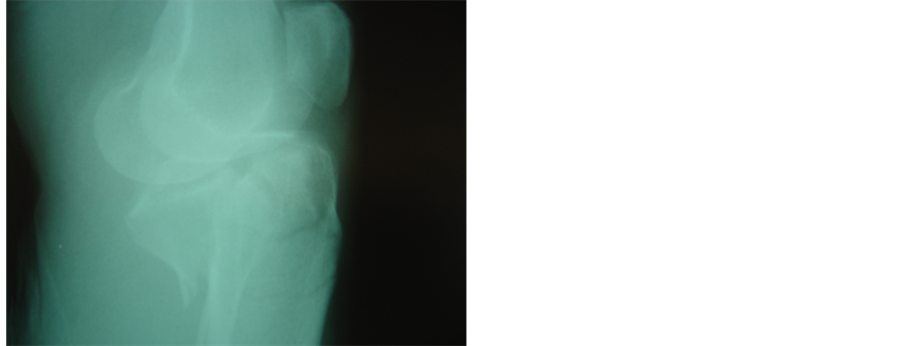

Operation was performed under epidural anesthesia. Preoperative assessment of radiographs and computerized tomography scans helped us achieve a good perspective of the fracture components. A tourniquet was applied only if the open method was to be used. Initially, when necessary, the knee hematoma was aspirated. Operation was then carried out under II control and always started with the application of one or more 6.5 millimeter canulated screws with washers, usually from the lateral side, parallel and as close to the articular surface as possible. At this stage, if needed, the articular surface was elevated by the use of a guide pin. Thus, the tibial plateau were reduced and compressed. Fixation was then completed with application of a hybrid external fixator (bridging the knee if required) or less invasive internal fixation with a limited lateral approach and an anatomic locking plate. Manual traction and various instruments (an owl or a large tenaculum reduction forceps or a tractor or use of a k-w like a joystick) were used to reduce the condyles [6] . Varus or valgus angulation was assessed very carefully and corrected. We did not perform ligament or meniscus repairs. All fractures were reduced with the knee closed. In case of instability, the knee was bridged with an extension of the hybrid to the lateral side of the femur [7] . We used a full ring, parallel to the articular surface and centered over the tibia, allowing close to 90˚ of knee flexion. We always applied two wires forming an x in axial viewing. These wires were placed within anatomically safe zones at the typical positions (posterolateral to anteromedial tibia through the head of the fibula and anterolateral to posteromedial). Then a third wire was inserted, usually between the first two and parallel to the articular surface in the AP view, but occasionally parallel and above the second one.. If an olive wire were used, it was inserted until the olive contacted the bone surface to apply extra compression. The wires were then fixed to the ring and tensioned. Three peripheral pins were applied, the fixator mounted and the fracture finally manipulated, reduced and stabilized (Figures 1(a)-1(d), Figures 2(a)-2(d)).

Figure 2. (a), (b): Schatzker IV fracture. Pre operative X-rays AP and Lateral; (c), (d): The fracture was treated with combination of hybrid fixator with one canulated screw. X-rays AP and Lateral three years later before removal of canulated screw.